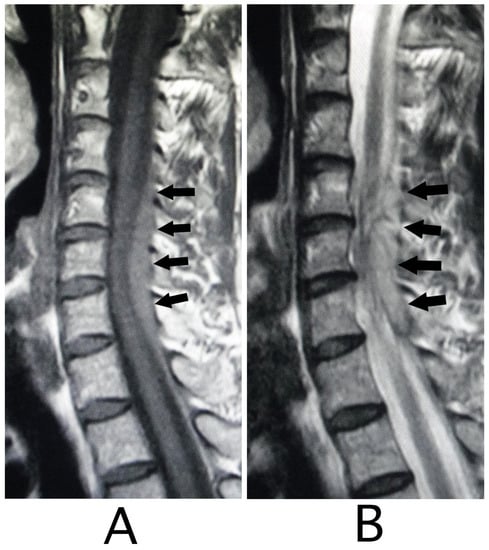

MRI of the spinal cord analysis was performed because the presence of acute lesions on the spinal cord was suspected, based on neurological findings and the clinical course. As a result, sagittal T1-weighted MRI showed an iso-intensity mass in the epidural space behind the spinal cord at the level from Th3 to Th6 (Figure 1A). Compression of the spinal cord was shown at the level between Th4 and Th6 (Figure 1A,B). The lesion was delineated as a high-intensity mass with heterogeneity and a superiorly adhered iso-intensity region in sagittal T1-weighted images (Figure 1B). Axial T1-weighted MRI showed an iso-intensity mass in the posterior part of the epidural space and a deviation of the spinal cord to the anterior direction (Figure 2A). The lesion was delineated as a heterogeneous high-intensity mass in axial T2-weighted MRI images (Figure 2B).

Figure 2. Axial MRI. An iso-intensity mass was identified in the posterior part in the epidural space (white arrows) (T1-weighted image; (A)). The lesion was delineated as a heterogeneous high-intensity mass (white arrows) (T2-weighted image; (B)). The spinal cord was compressed in the anterior direction (black arrows) (A,B). (Rt = right).